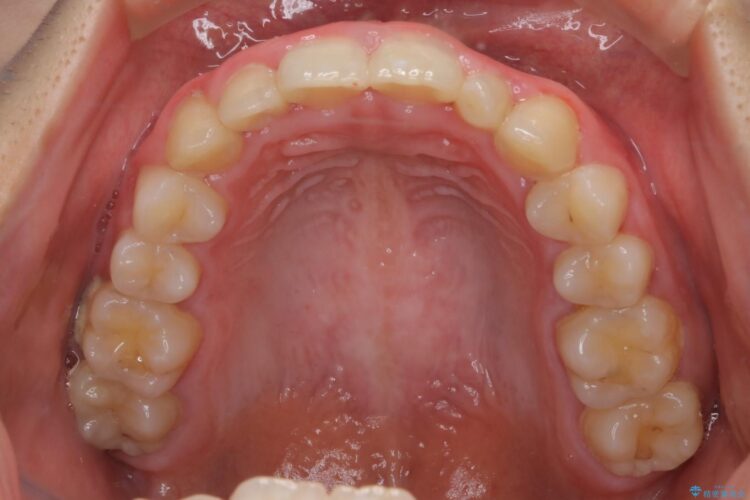

下の前歯のガタつきと正中のズレが気になるとご来院された患者様です。

軽度のガタつきだあったのと、かみ合わせがやや深かったため、インビザラインで治療を行うこととしました。

IPR(歯と歯の間を削る処置)と歯列拡大をすることでガタつきをとります。

前歯のガタつきを改善するのに時間がかかりましたが、ガタつきもかみ合わせも綺麗になりました。